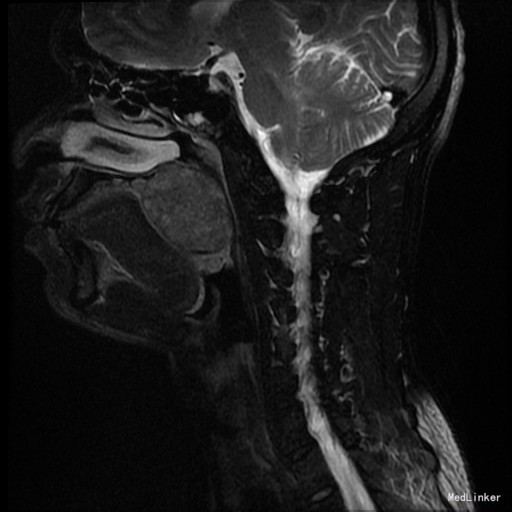

患者:男,42岁 主诉:发现右侧软腭肿物7年余。 病史:患者诉7年余前发现右侧软腭肿物,渐进性增大,无咽痛邓特殊不适。

查体:右侧软腭至硬腭处见一肿物,约5*3cm,质硬,固定,边界欠清,表面粘膜光滑。 辅助检查:外院颌面CT提示:右侧软腭实性占位,并累及鼻咽、口咽壁,建议MRI增强检查。

入院诊断:咽旁肿物(右侧软腭肿物性质待查) 治疗:入院后咽部MRI示:软腭右部软组织肿块,性质待定,鼻咽腔及口咽腔明显变窄。,未见手术禁忌,遂于全麻下行“右侧咽旁间隙肿物切除术”,术程顺利,术后未见并发症。病理:多形性腺瘤。